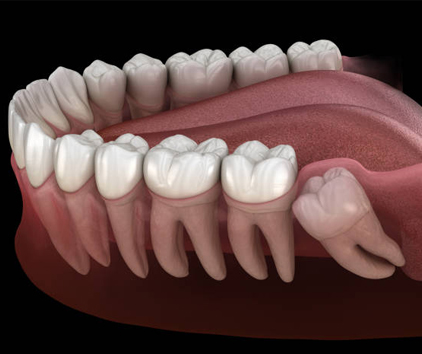

1. Impaction: When there’s not enough space in the jaw, wisdom teeth may become impacted, meaning they are unable to break through the gum line properly.

• The dentist will carefully remove the wisdom tooth, either through simple extraction or by making a small incision in the gum if the tooth is impacted.